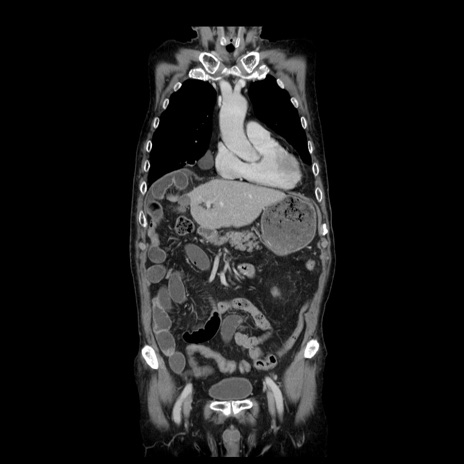

症例21(冠状断像)

【症例】70歳代男性

【主訴】腹痛

【現病歴】肝硬変・肝細胞癌にてかかりつけの方。約9時間前に食後より腹痛出現。症状が徐々に増悪し、嘔吐出現したため来院。

【既往歴】肝硬変、肝細胞癌(RFA、TACE後)

【身体所見】意識清明、表情苦悶様、BT 36℃、BP 129/78mmHg、P 88bpm、SpO2 97%(RA)、右上腹部から心窩部にかけて圧痛あり、反跳痛なし、筋性防御あり。

【データ】WBC 5800、CRP 0.16